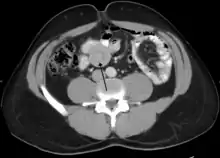

An intussusception is often suspected based on history and physical exam, including observation of Dance's sign. A digital rectal examination is particularly helpful in children, as part of the intussusceptum may be felt by the finger. A definite diagnosis often requires confirmation by diagnostic imaging modalities. Ultrasound is the imaging modality of choice for diagnosis and exclusion of intussusception, due to its high accuracy and lack of radiation. The appearance of target sign (also called "doughnut sign" on a sonograph, usually around 3 cm in diameter, confirms the diagnosis. The image seen on transverse sonography or computed tomography is that of a doughnut shape, created by the hyperechoic central core of bowel and mesentery surrounded by the hypoechoic outer edematous bowel.[10] In longitudinal imaging, intussusception resembles a sandwich.[10] It is also called "pseudokidney" sign because hyperechoic tubular centre is covered by a hypoechoic rim producing a kidney-like appearance.[11]